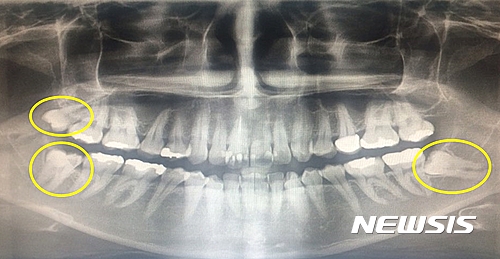

보통 성인의 경우 28개 치아 개수에 비해 턱이 작기 때문에 사랑니가 온전히 나오지 못하고 누워서 나거나 삐뚤게 되는 경우가 대부분이다. 특히 잇몸 안에 묻혀 보이지 않는 매복사랑니의 경우 육안으로는 식별이 불가능해 사랑니가 없는 것으로 생각하다가 통증을 느끼는 경우가 많다.

사랑니 존재 여부는 엑스레이 검사로 간단히 확인할 수 있다. 옆으로 누워난 사랑니의 경우 통증 없이 앞어금니까지 충치가 생기게 하는 경우가 많아 미리 검진을 받고 통증이 없더라도 예방 차원에서 발치하는 것이 좋다.